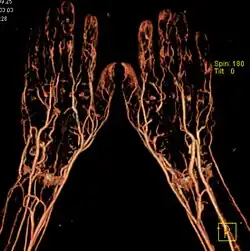

Angiograf rukou

Angiografie (také standardní nebo konvenční angiografie, digitální subtrakční angiografie (DSA), angiografické radiologické zobrazování cév) je lékařská zobrazovací metoda patřící do oboru radiologie. Při angiografickém vyšetření se zobrazují cévy (tepny a žíly) a také srdeční komory po předchozím vstříknutí kontrastní látky a následném snímkování rentgenem. Na snímku diagnostikované oblasti těla je pak vidět vnitřek cévy vyplněný kontrastní látkou. K provedení angiografie bez kontrastní látky lze využít magnetickou rezonanci, což ušetří invazivní punkci cévy.